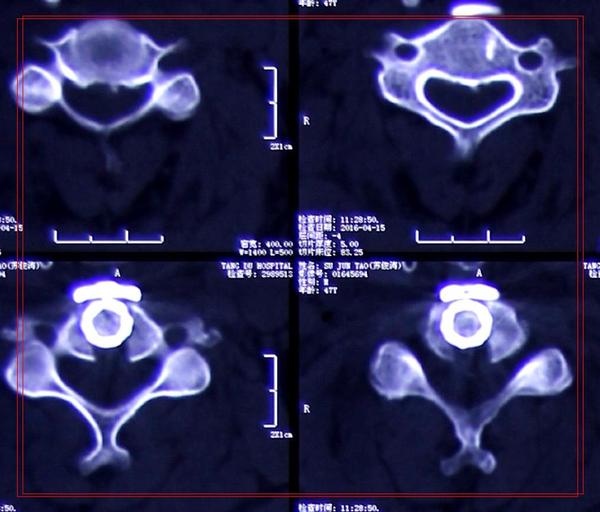

治疗:显微镜下单节段颈椎间盘切除植骨融合内固定术

影像学资料